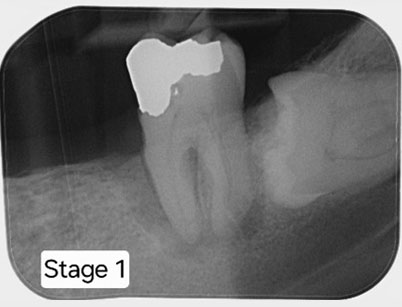

After removing the old crown, the RCT is completed

Posts are placed for a new crown.